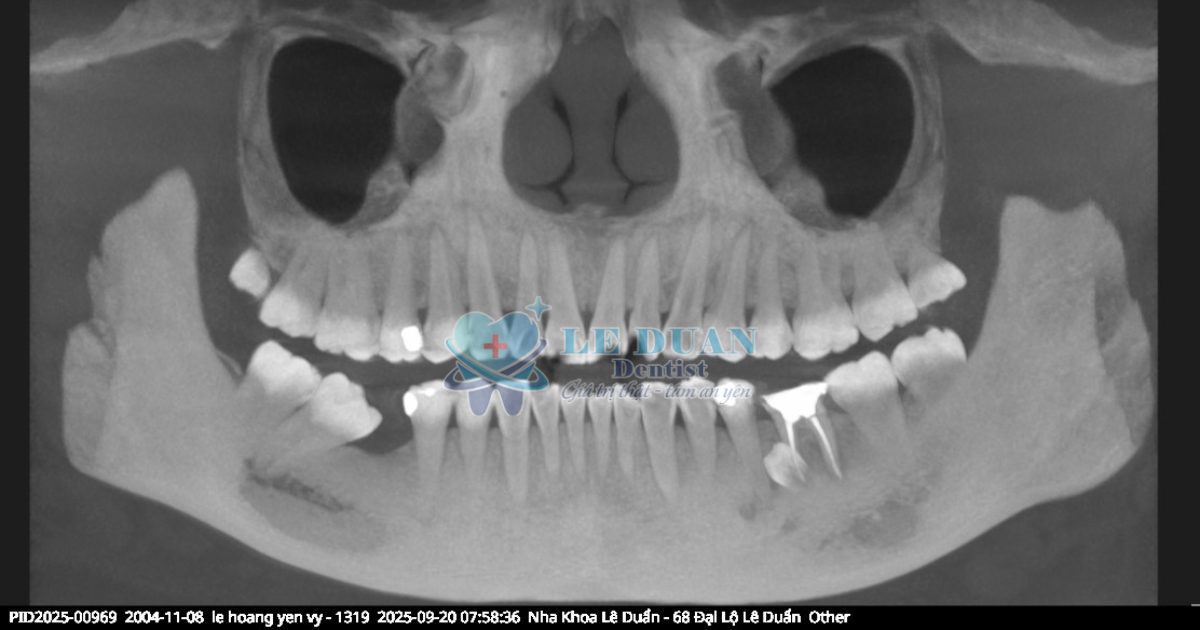

Ca răng mọc ngầm hiếm gặp giữa răng số 35 và 36 gây đau kéo dài. Khách từng đi nhiều bệnh viện tuyến đầu nhưng không tìm ra hướng điều trị. Tuy nhiên, đã được giải quyết nhẹ nhàng tại Nha Khoa Lê Duẩn.

Dưới phim chụp CT 3D Conebeam, bác sĩ phát hiện một mầm răng mọc ngầm nằm sâu trong xương hàm, chèn giữa 2 chân răng 35–36, gây chèn ép và viêm vùng mô quanh.

Đây chính là nguyên nhân gây đau kéo dài nhưng khó phát hiện bằng khám thông thường. Có thể thấy qua phim chụp CT 3D Conebeam, toàn bộ răng vĩnh viễn của khách hàng đã mọc đủ 32 răng. Vậy mầm răng mọc ngầm tại vị trí giữa chân răng 35 -36 là răng dư.